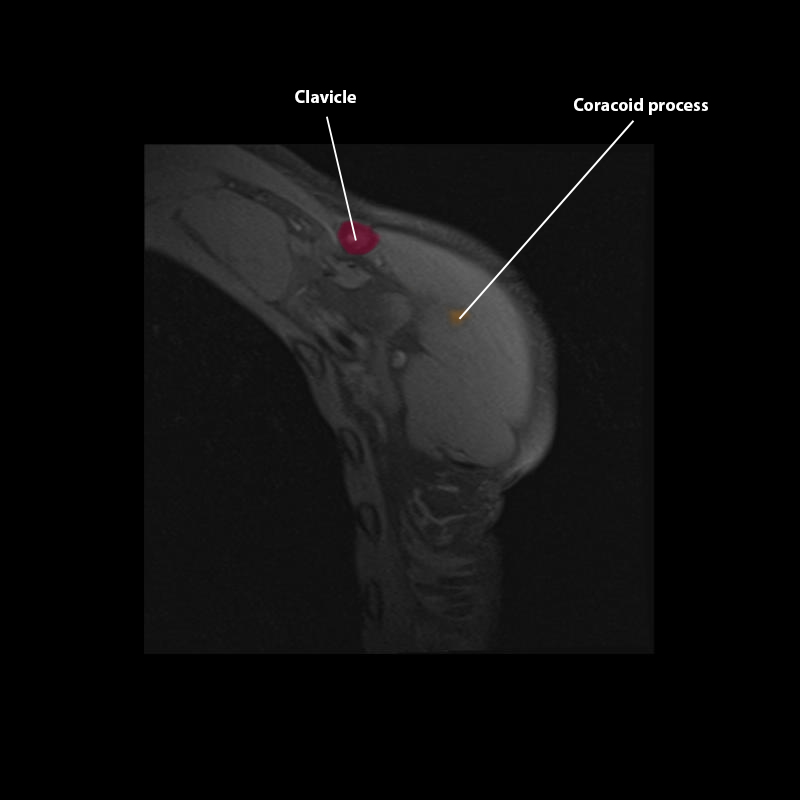

Shoulder MRI Anatomy